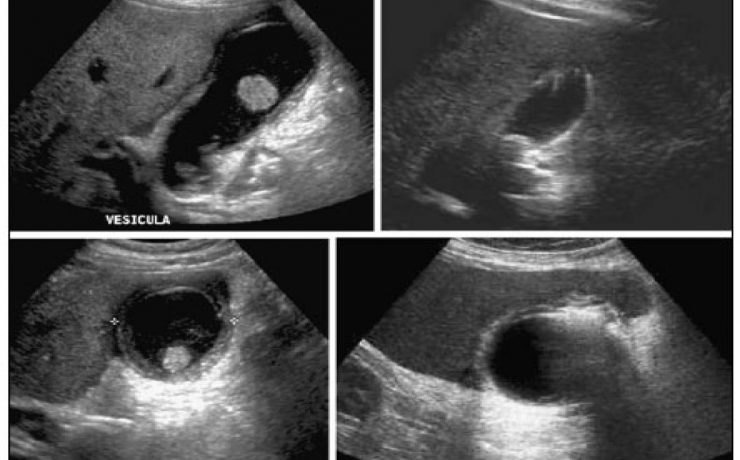

La ultrasonografía es un método útil, accesible, no invasivo y barato para realizar de forma confiable la medición del tamaño renal. La estimación del tamaño renal por ultrasonido puede realizarse por medición de la longitud, el volumen total o el grosor cortical. El tamaño renal depende de algunos factores que